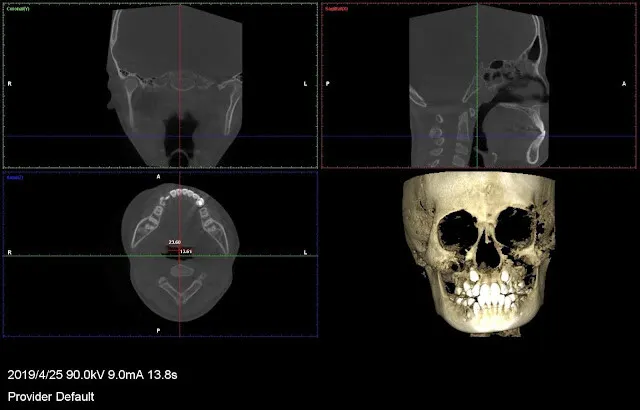

以上是CT斷層掃瞄,我會測量呼吸道(氣管咽喉部分)的寬度,有數值的,一張是平均,一張是最窄處。